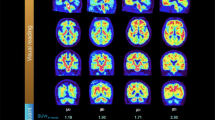

When we considered clinical stages, we found a substantial rise in tau load as measured by global SUVR from CU to DEM (p<0.001) (Table 3). Tau positivity increased regardless of the tau assessment’s methods (Table 3). Using global SUVR resulted in the highest T+ rates, for all clinical diagnoses, independently from Aβ status, with T+ rate progressively increasing from CU to MCI to DEM in Aβ-positive participants. Visually defined T+ rates progressively increased from CU to MCI to DEM in Aβ-positive participants, with the lowest T+ rates observed in Aβ-negative participants, reaching zero in Aβ-negative CU. STOC-based T+ rates fell between visual- and global SUVR-based rates in CU, were similar to visual assessment in MCI, and exhibited lower rates in DEM, ultimately reaching zero T+ in Aβ-negative CU (Fig. 1 and Table 3).

Distribution of tau-positive patients by modality, clinical diagnosis, and amyloid beta status. Tau positivity is represented as percentages. Results based on global SUVR, visual Braak staging and STOC staging are shown in blue, red, and green, respectively. Abbreviations: CU, cognitively unimpaired; MCI, mild cognitive impairment; DEM, dementia; A, amyloid; STOC, Simplified Temporo-Occipital Classification